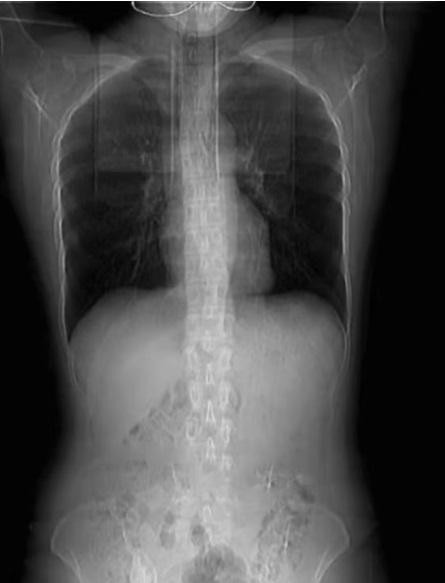

Kết quả chụp cắt lớp cho thấy 4 xương sườn của Huang đã gãy. Các bác sĩ nói rằng, Huang còn cần phải quấn băng quanh ngực trong 1 tháng đồng thời nghỉ ngơi.

| Người phụ nữ lên cơn ho vì thức ăn cay làm gãy 4 chiếc xương sườn. Ảnh: SCMP. |